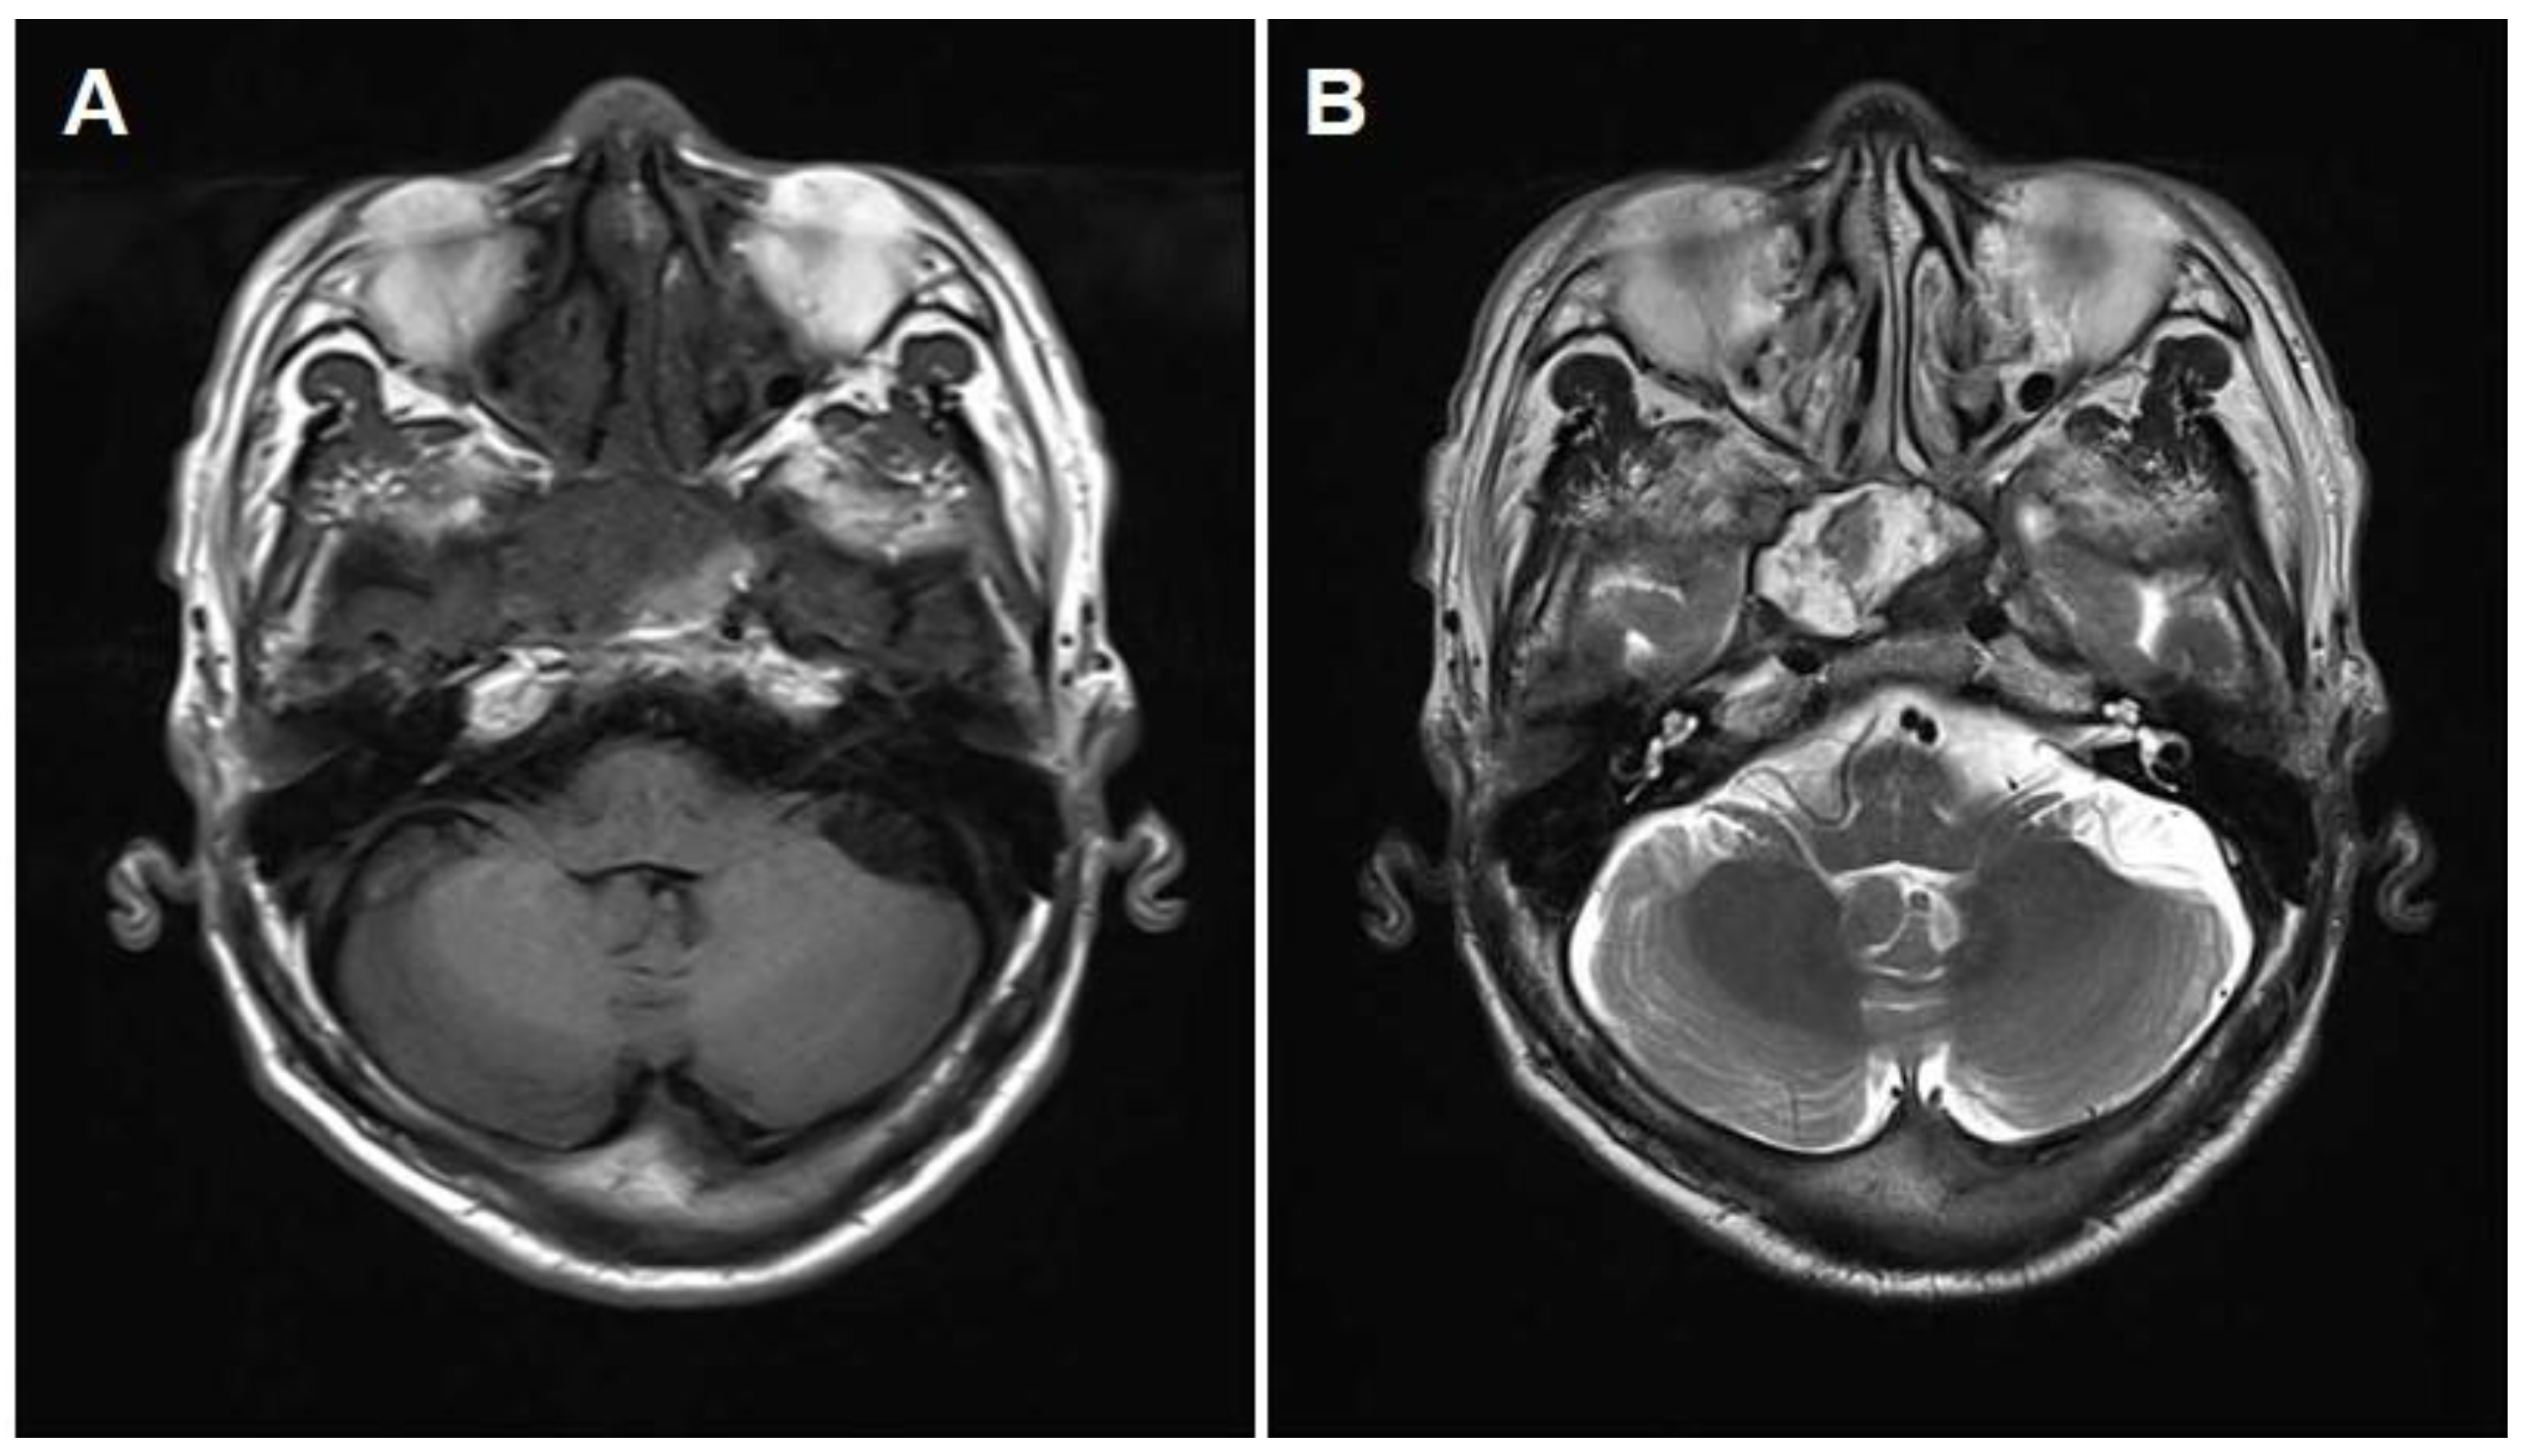

2. Case Report